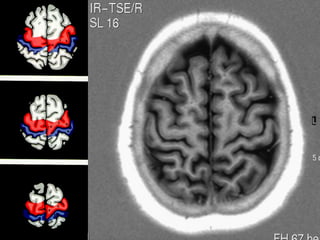

Anatomia cerebral

VENTRÍCULOS CEREBRAIS

• 4 cavidades que se intercomunicam,

( VL D e E , III, IV ),

• Contém plexos coróides ,

• Comunicações entre VL --- III ( forames de Monro),

III --- IV ( aqueduto de Sylvius ),

IV ---- espaço subaracnoideo

( 2 forames de Luschka e 1 forame de Magendie - central )

VENTRÍCULOS LATERAIS

• Cavidades extensas e irregulares dentro

dos hemisférios cerebrais.

• Limites - superior      corpo caloso

medial      septo pelúcido

inferior    parte do tálamo

núcleos caudados ,trígono.